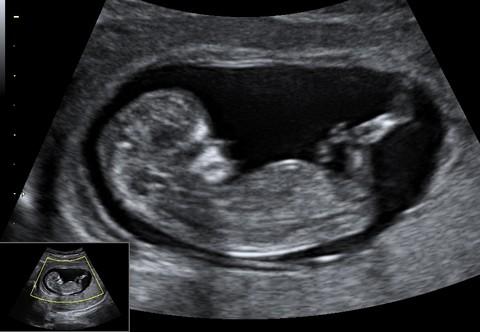

Plod stáří 11+2 týdne a velikosti 47 mm. Je vidět hlava s nosem, jasnější horní a dolní čelistí. Vpravo pak dolní končetiny.